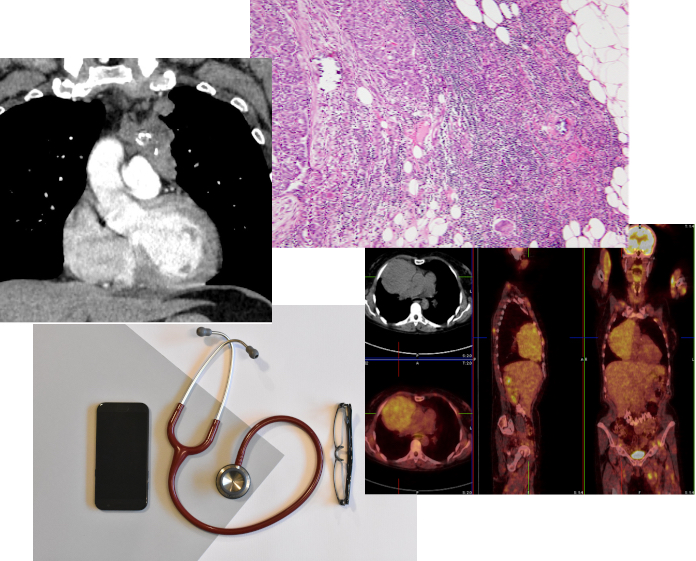

Artificial Intelligence Working Group

Jan von der Thüsen

The ITMIG AI working group aims to provide advice and a meeting place to those interested in setting up / supporting mediastinal AI projects in mediastinal diseases. Over the past year its members have been drafting a survey on the attitudes towards, experience of, and requirements for the use of artificial intelligence in thymic epithelial tumours (TETs). The working group is currently finalizing the draft survey, which will be shared with clinical colleagues for feedback prior to roll-out across the membership of ITMIG. As TETs are rare, and AI models are data-hungry and require external validation, collaboration between centres to increase the number of cases, especially of ultra-rare variants of TET to address class imbalance, is imperative. ITMIG offers a unique platform to facilitate this type of collaboration, and we have been carefully exploring possibilities for data transfer according to international regulatory practices. This work is currently still ongoing, but once complete, the first model to be developed will try to predict intra-class recurrence patterns of early-stage TETs. The working group has a virtual meeting every first Friday of the month, and welcomes new members, especially clinicians and radiologists!